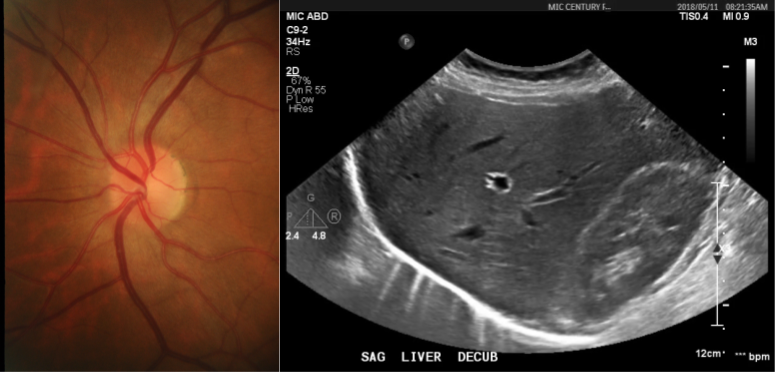

The machine learning task is to produce a model that predicts if an ultrasound image of the liver (see Figure 5, right) should be diagnosed as fatty, or normal. We used a private dataset that contains 505 images, with labels made by an expert radiologist. We placed 353 (70%) in the training set, and the remaining 152 in the hold out set. The percentage of normal cases in both sets was 62%.

Similarly to the experiment with hip dysplasia, we first trained a probabilistic model to encode the medical knowledge. Hamer et al. (2006) reports that the diagnosis of fatty liver depends on the difference in echogenicity among the liver, diaphragm, and the periportal zone [12] – more precisely, an increased hepatic echogenicity that obscures the periportal and diaphragm echogenicity suggest a liver is fatty [19].

We manually defined regions of interest over the relevant anatomical parts in the images, and extracted their mean pixel intensity. The vector Z=[m1,m2,m3]𝑍subscript𝑚1subscript𝑚2subscript𝑚3Z=[m_{1},m_{2},m_{3}] contains the mean intensity value of the regions of interest extracted (respectively) from liver, diaphragm and periportal zone. This time, we modelled P(Y|Z)=σ(ZTθ)𝑃conditional𝑌𝑍𝜎superscript𝑍𝑇𝜃P(Y\ |\ Z)=\sigma(Z^{T}\theta), where σ()𝜎\sigma(\cdot) is the sigmoid function. We then use the probabilistic labels P(Y|Z)𝑃conditional𝑌𝑍P(Y\ |\ Z) to train a network with the same architecture described in Section 4.2, and perform the comparison among models trained with hard, soft, and probabilistic labels. Table 1 shows the results.

Refer to caption

Figure 5: Typical images used for the diagnosis of glaucoma (left) and fatty liver (right).

4.4 Experiment 4: Glaucoma

Here, we wanted to learn a model that classifiers the fundus image of a retina (Figure 5, left) as healthy, or as suspicious of glaucoma. We used the publicly available dataset RIM-ONE r3 [4], which contains 85 images classified as normal, and 74 as suspects of glaucoma. We used 70% of the data for training purposes, while the remaining 30% was used as hold-out set. We kept the same healthy over glaucoma ratio in both datasets. Besides the diagnosis, which we used as ground truth, the dataset contains the masks of the disc and the cup masks of the optic nerve.

MacCormick et al. (2019) identifies the vertical and horizontal cup-to-disc-ratio as an important feature for the diagnosis of glaucoma [22]. The vector Z=[r1,r2]2𝑍subscript𝑟1subscript𝑟2superscript2Z=[r_{1},r_{2}]\in\mathbb{R}^{2} contains these vertical and horizontal ratios. We assumed that the data comes from a mixture of 2 bi-variate Gaussians (one per each class) and, after learning the parameters of the probabilistic model, we used Eq. 6 to compute the probabilistic labels.